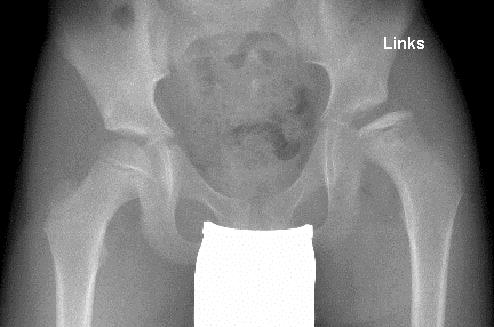

File Radiografia Leg Calve Perthes Jpg Wikimedia Commons

File Radiografia Leg Calve Perthes Jpg Wikimedia Commons from upload.wikimedia.org